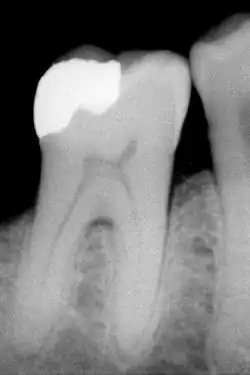

L'amalgame

C'est le matériau le plus ancien. Couramment appelé plombage, il ne contient pas de plomb. L'amalgame dentaire est constitué de mercure, d'argent, de cuivre, d'étain, de zinc… La proportion de ces métaux détermine le type d'amalgame. Les amalgames de dernière génération appelés « HCSC » (pour High copper single composition) sont à haute teneur en cuivre.

- La technique directe, consiste à placer un matériau en phase plastique (c’est-à-dire mou) dans la cavité résiduelle et de l'y faire durcir. Les matériaux que l'on peut utiliser sont : les amalgames, les résines composites, les verres ionomères ainsi que de nombreux matériaux hybrides mélange des précédents. Cette technique a comme avantage d'être rapide, simple et peu onéreuse. En revanche, elle est peu pérenne du fait que l'interface entre le matériau et la dent (appelé le joint) est large.

- La technique indirecte consiste à prendre l'empreinte de la cavité que l'on veut obturer, le prothésiste fabrique ensuite la pièce juste manquante. Les matériaux pouvant être utilisés sont : les métaux et alliages métalliques (or, nickel-chrome, chrome-cobalt), la résine cuite, la céramique (ou porcelaine). La pièce issue de cette technique s'appelle un inlay. Quand la cavité est très grosse et que des parties entières de dents sont à reconstruire, on les appelle onlay. Cette technique a comme avantage d'être très pérenne, très satisfaisante esthétiquement (sauf quand le matériau utilisé est métallique), mais extrêmement onéreuse (de 10 à 20 fois le prix d'une restauration par technique directe).